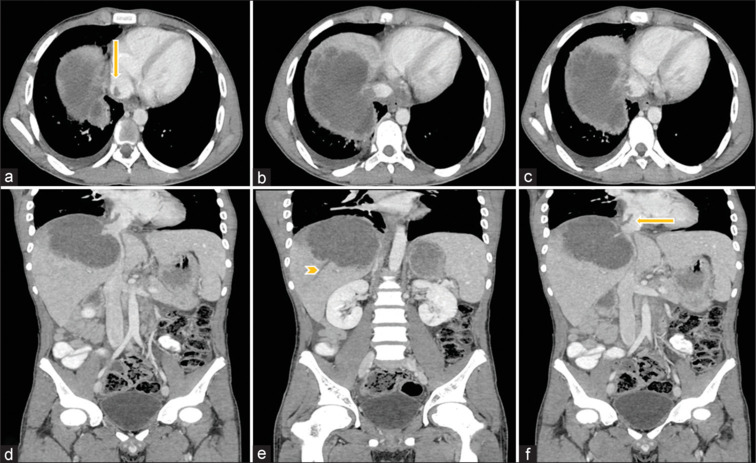

阿米巴病是一种寄生虫感染,阿米巴肝脓肿(ALA)是最常见的肠外表现。ALA的常见并发症包括破裂进入胸膜、心包或腹膜腔。罕见的是,它们会引起血管并发症,如肝静脉和下腔静脉血栓形成,这些静脉可能进一步延伸到右心房或栓塞导致肺血栓栓塞。在本研究中,我们报告了三例ALA患者的血管并发症。血管病变的存在不应错过。通过及时发现和治疗,可以预防血管并发症的发展。

Amebiasis is a parasitic infection with amebic liver abscess (ALA) being the most common extraintestinal manifestation. Common complications of ALA include rupture into the pleural, pericardial, or peritoneal cavity. Uncommonly, they can cause vascular complications such as thrombosis of the hepatic vein and inferior vena cava which may further extend to the right atrium or may embolize resulting in pulmonary thromboembolism. In this study, we report three patients with vascular complications in ALA. The presence of vascular pathology in ALAs should not be missed. With its detection and prompt treatment, the progression of vascular complications can be prevented.